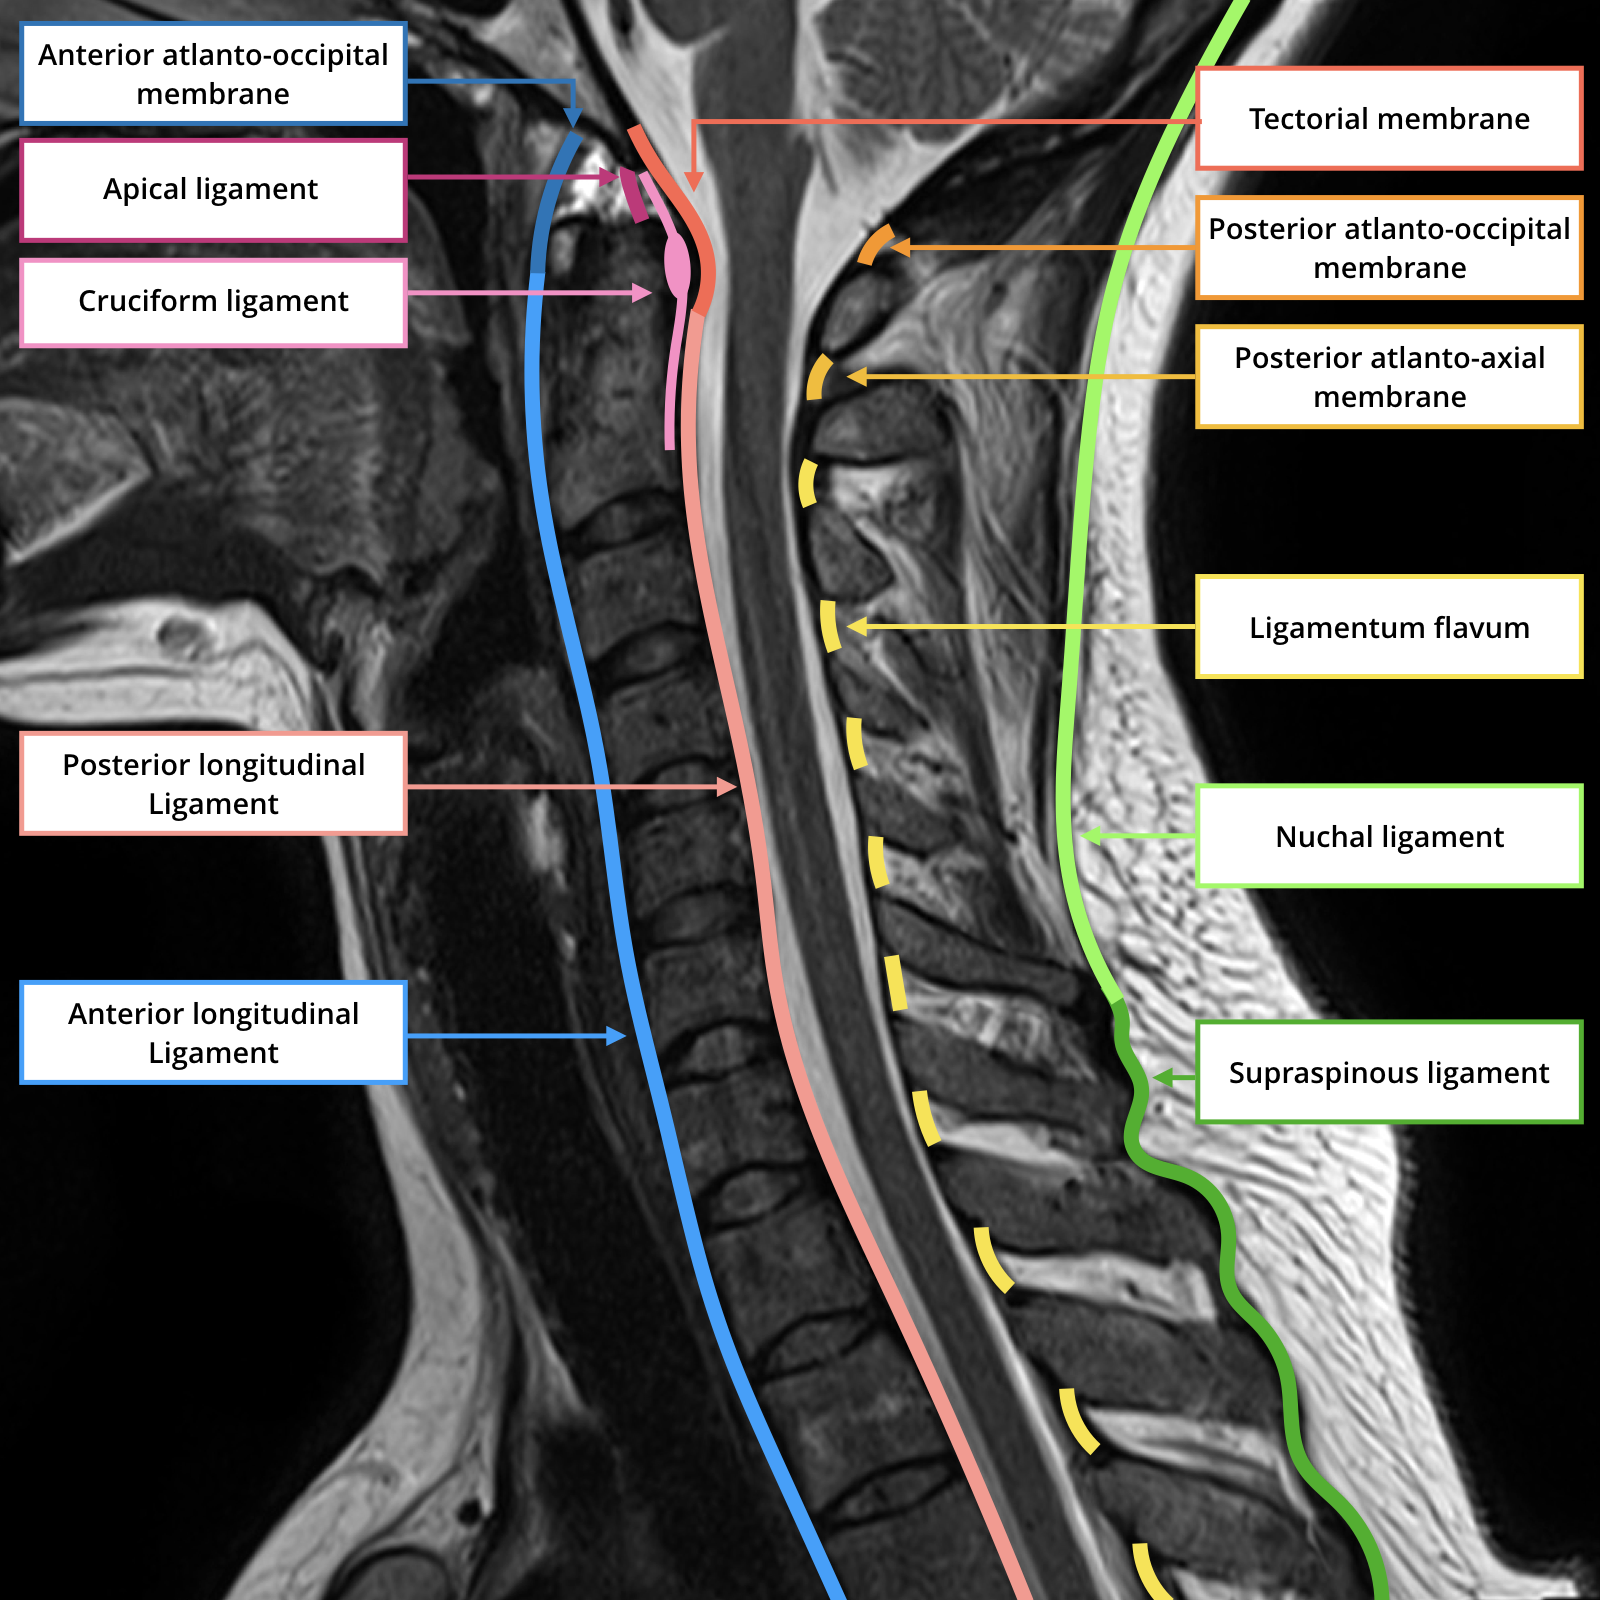

Apical ligament

• Attaches the tip of the dens to the anterior aspect of foramen magnum

• Weak

• Fibrous remnant of notochord

Cruciate Ligament

• 2 parts

• Longitudinal

• Body of C2 to clivus & foramen magnum

• Does not contribute to stability

• Transverse part (seen on CT below)

• C1 lateral masses to tectorial membrane and dura

• Runs posterior to dens

• Strong and provides stability